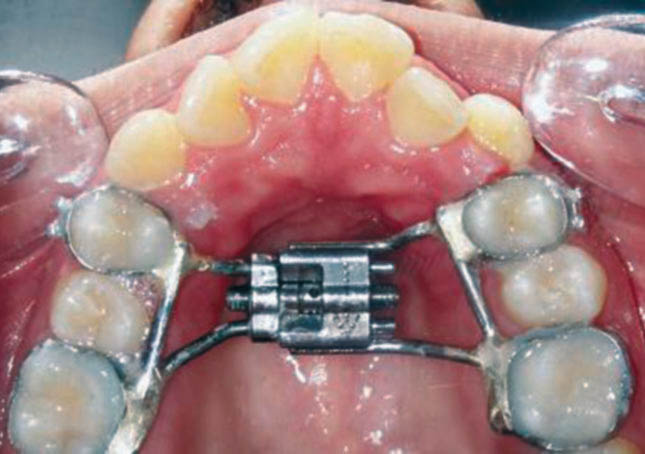

برای این بیماران ابتدا سپراتور خلفی در مزیال و دیستال دندانهای پرمولر اول و مولر اول بالا میگذاریم (شکل 77-3). هفته بعد سپراتورها را خارج میکنیم و چهار بند با سایز مناسب روی این دندانها میگذاریم. ترجیحاً یک شماره بزرگتر از نرمال باشند تا بعد از لحیم کاری، پیچ با سختی جا نرود. یک قالب آلژینات pick up از این بندها میگیریم. بندها را از روی دندانها خارج میکنیم و درون آلژینات میگذاریم (شکل 78-3). در زمانی که قالب pick up را به لابراتوار ارسال میکنید مجدداً سپراتورهای خلفی را قرار بدهید تا فضای اطراف دندانهای پرمولر و مولر اول بسته نشود.

گچ آن را میریزیم و بعد از سفت شدن گچ، به لابراتوار ارسال میکنیم تا پیچ مخصوص آن را روی این چهار بند فرم بدهند و لحیم کنند.

قبل از ارسال به لابراتوار حتماً دقت نمایید که بندها در جایگاه صحیح باشند (شکل 79-3) چون اگر در زمان ریختن گچ بندها تکان بخورند و در جایگاه صحیح خود نباشند، بعد از اتمام لحیم کاری، پیچ بر روی دندانها تطابق خوبی نخواهد داشت و حالت الاکلنگی پیدا میکند.

این پیچ به کمک این چهار بند روی دندانهای قوس بالا سمان میشود (شکل 80-3).

شکل 77-3: قرار دادن سپراتور در مزیال و دیستال پرمولر اول و مولر اول

شکل 78-3: قالب pick up از بندهای پرمولر اول و مولر اول

شکل 79-3: جایگاه صحیح بندها بعد از ریختن گچ قالب آلژیناتی pick up

شکل 80-3: نصب پیچ RPE روی دندانها